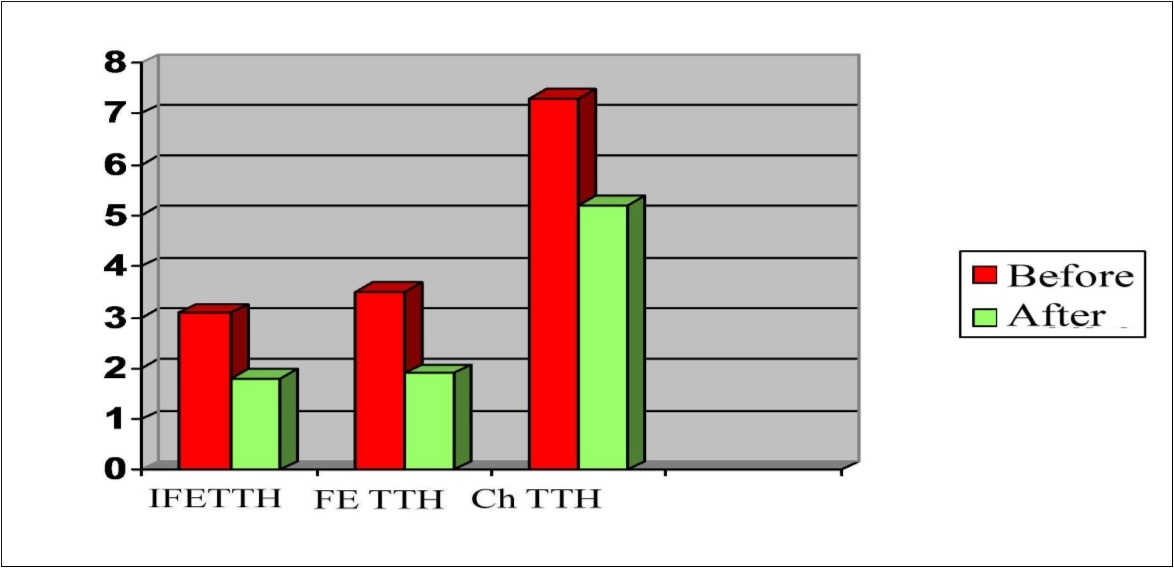

In patients with TTH, hyper-responsiveness to hypercapnic test was detected: RcCO2 was 1.43±0.05 in the group with FE TTH; 1.39±0.07 in the group of Ch TTH and 1.37±0.04 in the group of IFE TTH, which indicates a tendency for the tension of the vasodilator regulation mechanism even in clinically insignificant forms of TTH. In the study of reactivity to the O2-test, a hyporeactive response was observed in the groups with FE TTH and Ch TTH (0.38±0.04 and 0.35±0.05), respectively (Figure 3). As can be seen from Figure 3, in all groups, the reactivity coefficient (Rc) when performing functional tests using CO2 and FMt was significantly higher than using O2 (P <0.001).

Figure 3.Parameters of reactivity coefficient (Rc) to the CO2, O2 and FMt test in a patients with TTH.

As can be seen from Figure 4 similar results were obtained with the antiorthostatic test (RcAOt) compared with the results of the orthostatic (RcOt) and functional test with nitroglycerin (RcFNt). However, in the study of reactivity to orthostatic, nitroglycerin and antiorthostatic tests there were no significant differences between the parameters of patients with IF TTH, FE TTH, Ch TTH and CG.

Figure 4.Parameters of reactivity coefficient (Rc) to the orthostatic test (Ot), antiorthostatic test (AOt) and functional nitroglycerin test (FNt) in a patients with TTH.